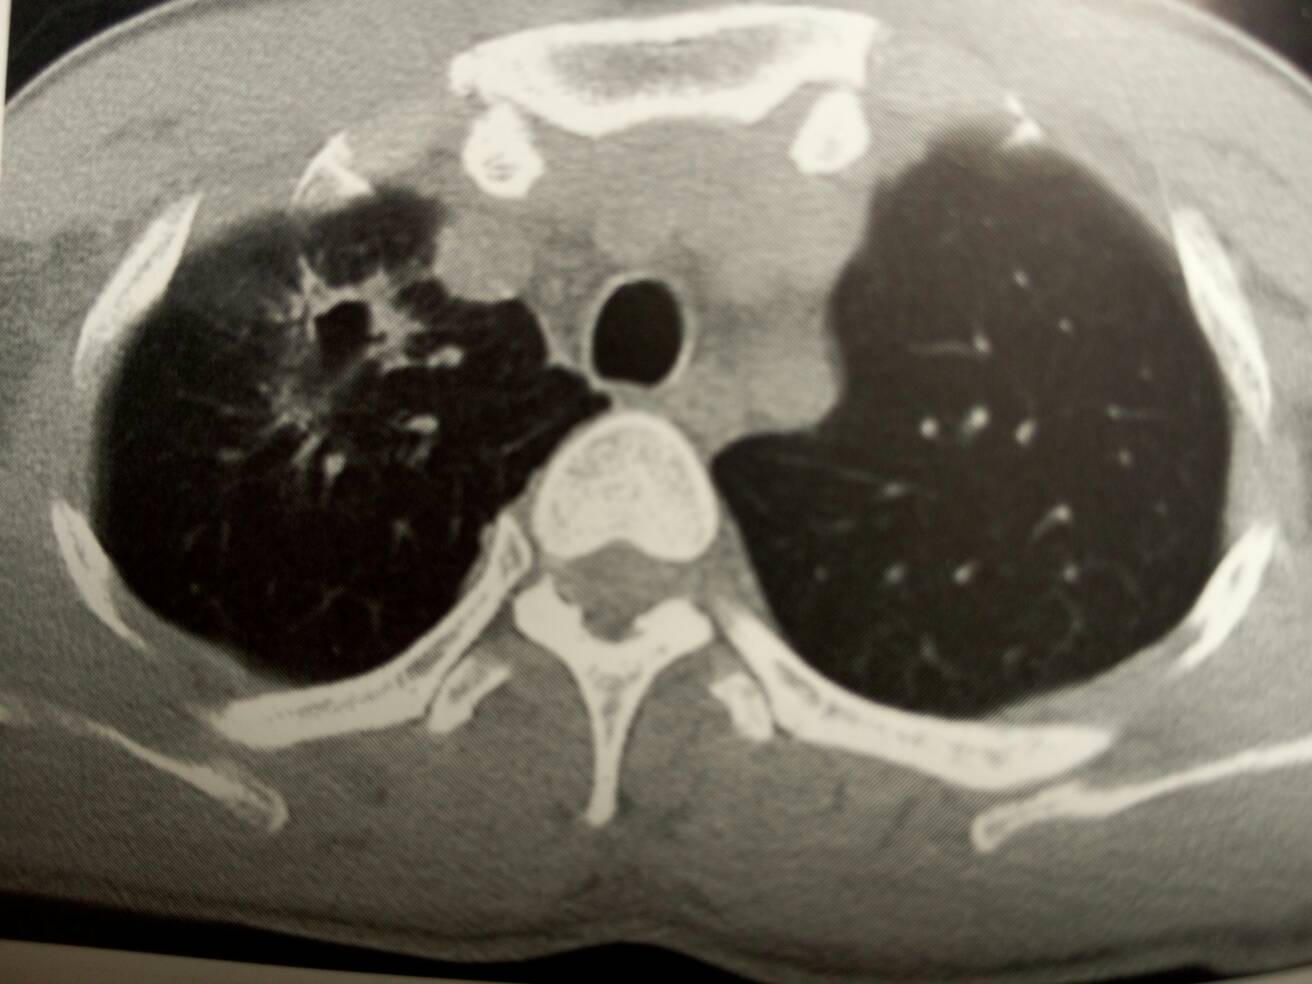

男,40岁。反复咳嗽咳痰半年。CT:右肺尖脓肿。抗炎后4周病灶明显缩小。